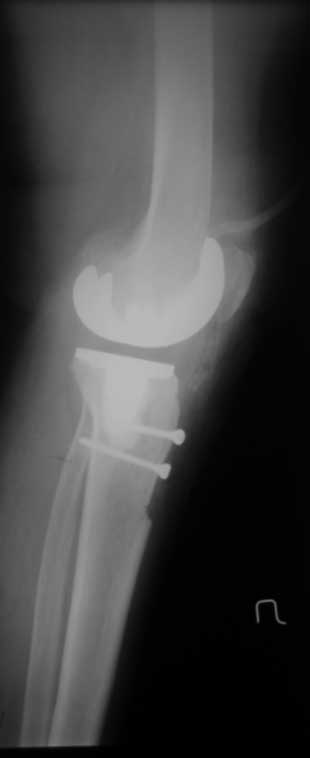

По данным R-грамм, хотя качество их не очень..., мне кажется имеется 2 основных ошибки: 1. высокий уровень остеотомии большеберцовой кости, при разгибетельных контрактурах его необходимо делать ниже.

2. Большой размер бедренного компонента. За счет этого переднезадний размер увеличен и ограничивает сгибание.

>1. высокий уровень остеотомии большеберцовой кости, при разгибетельных контрактурах его необходимо делать ниже.

уверяю вас, бедренный офсет не увеличен (снимок в ротации - ближайший п/о период, сложно вывести проекцию) экспериментируя с опилами к имеющимся проблемам можно было получить несбалансированное колено. Опил тибии стандартный на 10-ый вкладыш. Без рефиксированной бугристости колено было отлично сбалансировано, сгибание было до острого угла. проблема была именно в мягких тканях, конкретно в разгибательном аппарате, а не в опилах

снимки